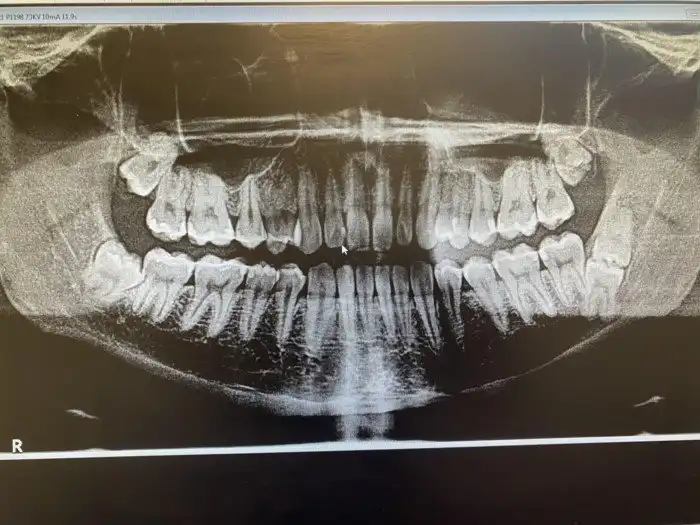

"У меня пять зубов мудрости"